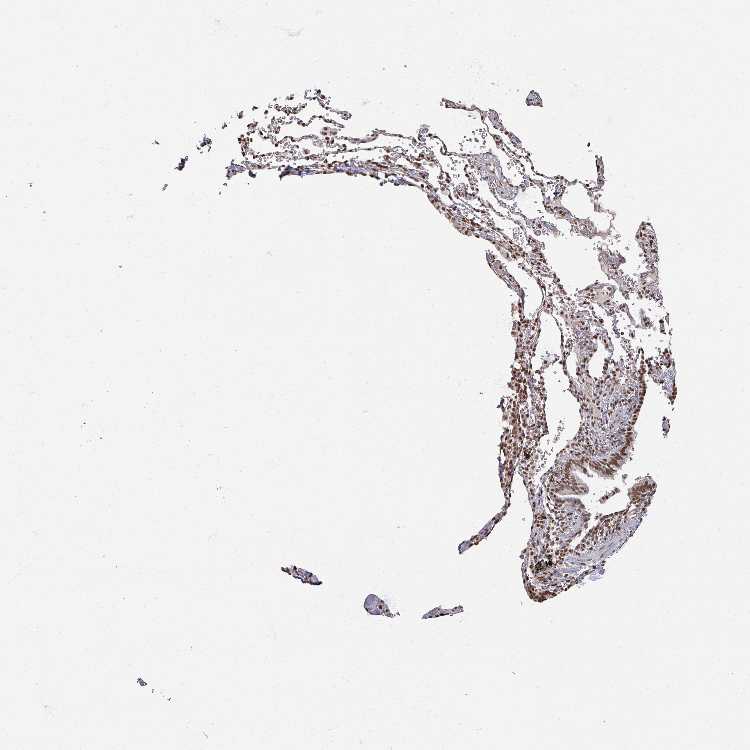

SOFT TISSUE 1 - Antibody stainingi

Antibody staining in the annotated cell types in the current human tissue is reported as not detected, low, medium, or high, based on conventional immunohistochemistry profiling in selected tissues. This score is based on the combination of the staining intensity and fraction of stained cells.

Each image is clickable and will lead to virtual microscopy that enables deeper exploration of all samples and also displays staining intensity scores, fraction scores and subcellular localization as well as patient and tissue information for each sample.

Antibody HPA050863

Fibroblasts Medium